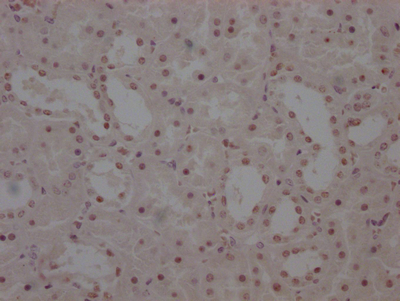

IHC image of CSB-RA169000A0HU diluted at 1:100 and staining in paraffin-embedded human liver cancer performed on a Leica BondTM system. After dewaxing and hydration, antigen retrieval was mediated by high pressure in a citrate buffer (pH 6.0). Section was blocked with 10% normal goat serum 30min at RT. Then primary antibody (1% BSA) was incubated at 4°C overnight. The primary is detected by a Goat anti-rabbit polymer IgG labeled by HRP and visualized using 0.05% DAB.